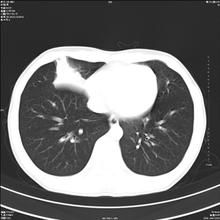

胸部X線檢查

胸部X線檢查對診斷幫助極大。

後前位:可見右側肺門下部、右心緣旁有密度均勻或略有增高的陰影成三角形陰影。其大小、形狀、位置和緻密度可因中葉不張的程度和炎症輕重的不同而不同。陰影上界較清楚,不超過肺門陰影的中位,以內側較密,其他部分邊緣不清楚。水平葉間隙多向下移位。,鄰近肺野可見代償性肺氣腫。

前弓位:可見一典型由肺門向外伸展的三角陰影,基底向縱隔,尖端向肺野,兩側邊緣銳利。此為中葉不張的特徵。

右側位:在中葉部可見前下方斜行的帶頭或條索狀、梭形陰影,水平裂與斜裂移位相靠近,陰影上端不超過肺門。並可觀察肺門部位有無腫塊或淋巴結鈣化情況。根據葉間隙的變化,側位易看出中葉肺不張的程度和胸膜粘連的情況,故側位片在該病徵的診斷更為重要。

胸部CT檢查可發現肺門淋巴結及支氣管狹窄腫瘤阻塞等。